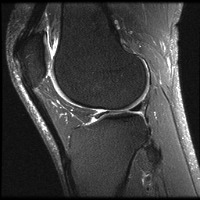

meniscal Computer Vision Project

Medical Diagnostics: Radiologists, orthopedic surgeons, and other medical professionals can utilize the "meniscal" model to accurately identify and classify meniscal lesions in knee MRI scans, thus improving the diagnosis and treatment process for patients with knee-related injuries and conditions.

Sports Injury Prevention and Management: Sports rehabilitation centers and athletic trainers can employ the "meniscal" model for analyzing knee scans of athletes to assess the health of their knees, track any changes over time, and tailor training regimens or treatments to prevent or recover from meniscal injuries.

Pre- and Post-Surgery Evaluation: Surgeons can use the "meniscal" model to analyze the knee scans taken before and after meniscal surgeries to evaluate the efficacy of the surgical intervention and make informed decisions about the patient's further treatment plan and rehabilitation process.